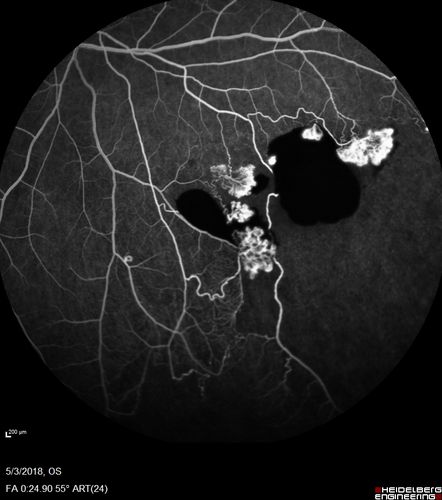

Coats' Disease -51 year old asymptomatic male

20/20 vision - had laser to non-perfusion because of proliferation.